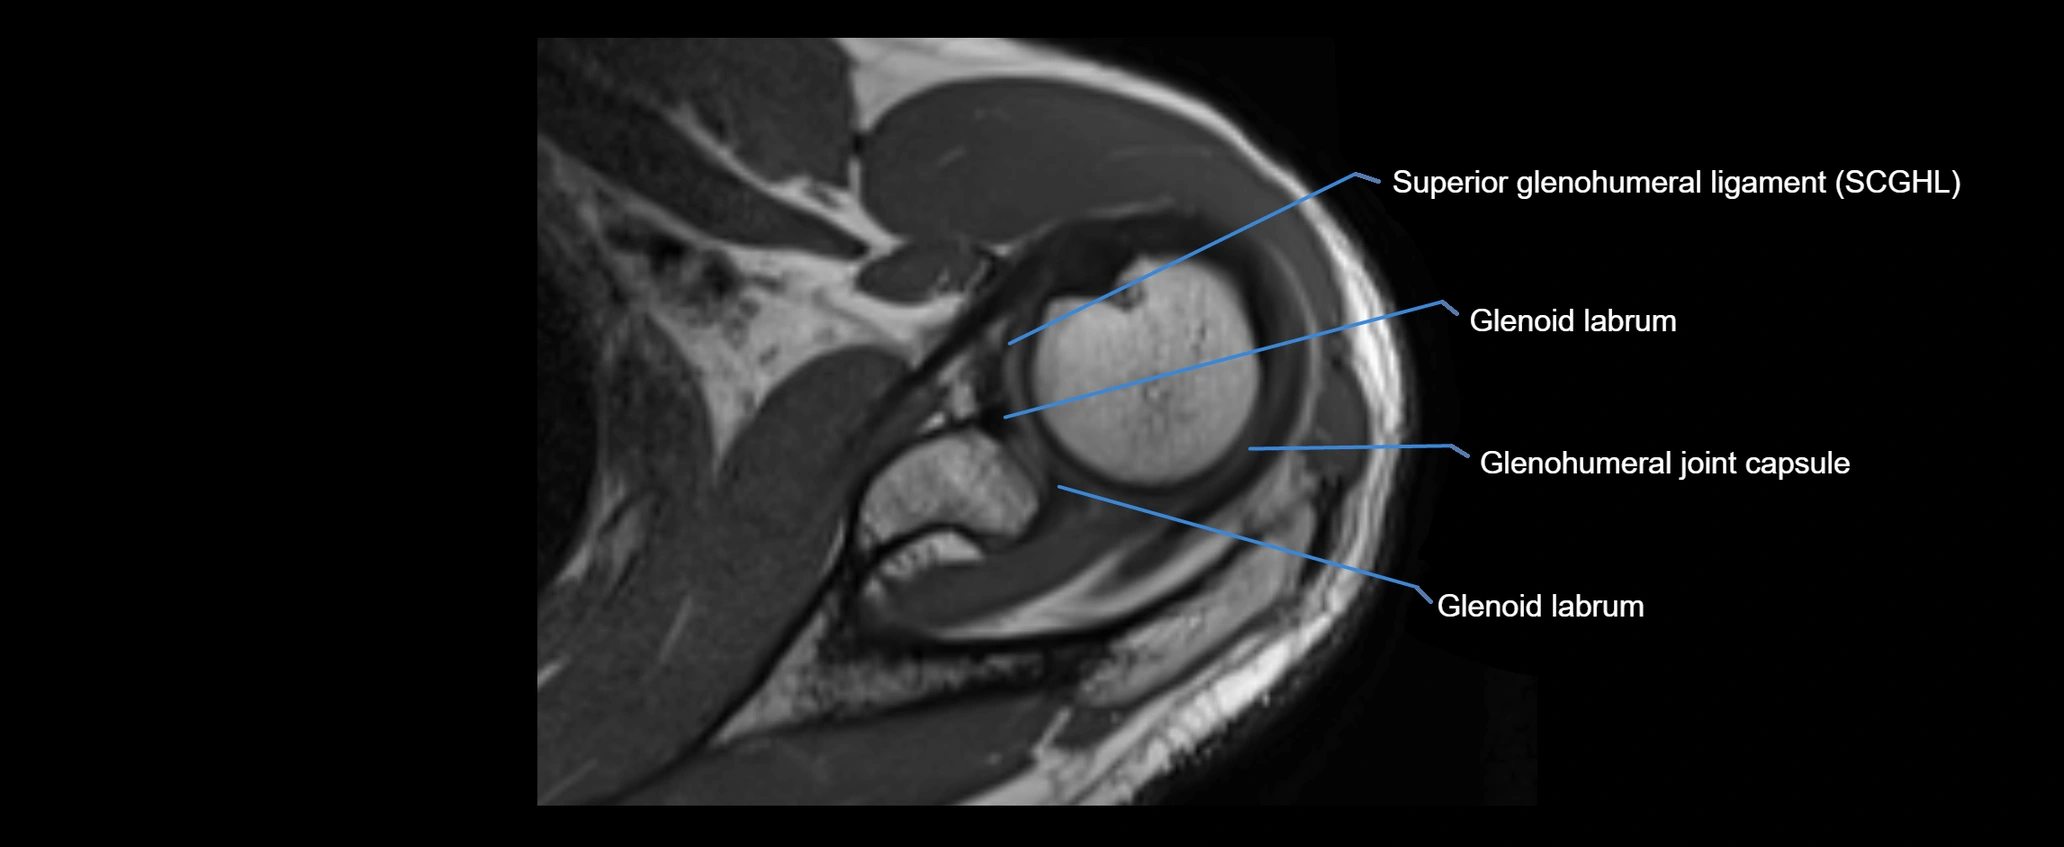

MRI images

image